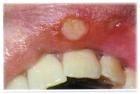

随着病情的逐渐发展,粘膜的部位开数逐渐的变红,形成白膜和红斑并存的现象,为红白相兼型;如果再进一步发展的话,可在发病的部位出现红斑和糜烂的特点,对患者的进食造成一定的影响,为红斑的糜烂型。

对于扁平苔藓病的患者来说,也有一开始就出现红斑或者是糜烂者。有的患者因长期得不到恰当的治疗,病损的部位出现硬结或者是高出的粘膜,这时,对于患者来说,应考虑有癌变的可能和危险。需要进行进一步的确认。